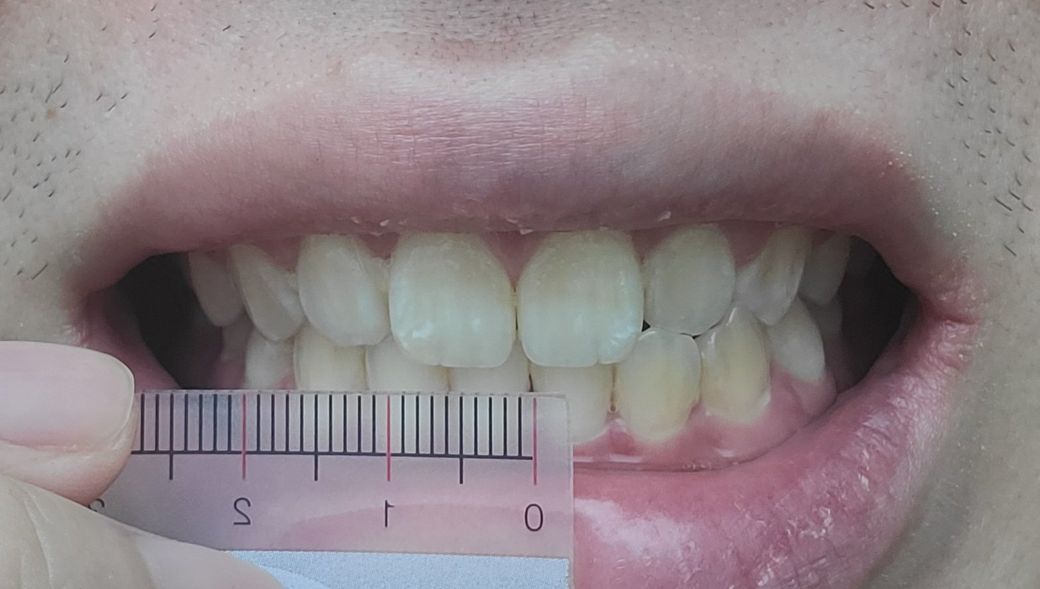

1. 치아중심선이 2mm정도 턱 뼈 비대칭이 3mm정도 틀어져있다는데 정상범주 인가요?

• 1번 째 사진